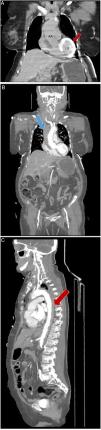

Computed tomography showed myocardial contrast retention in the left ventricle wall (Figure 4A). An aneurysmal dilatation of the AA with associated intramural hematoma and an intimal flap extending distally were noted, compatible with Stanford type A AD (Figure 4B and C). She suffered a cardiac arrest with pulseless electrical activity, recovered after 12 minutes of advanced life support, and was transferred to a cardiothoracic surgery centre. On admission to this center, she presented echocardiographic signs of retrograde dissection, with aortic regurgitation, and no clinical conditions for performing surgery. The patient died a few hours later.

(A) Coronal computed tomography. Non-contrast-enhanced coronal computed tomography showing myocardial contrast retention in the left ventricle wall (red arrow). (B) Coronal computed tomography. Contrast-enhanced coronal computed tomography showing intramural hematoma in ascending aorta (blue arrow). (C). Axial computed tomography. Contrast-enhanced axial computed tomography showing intramural hematoma in descending aorta (red arrow). AA: ascending aorta; LV: left ventricle.